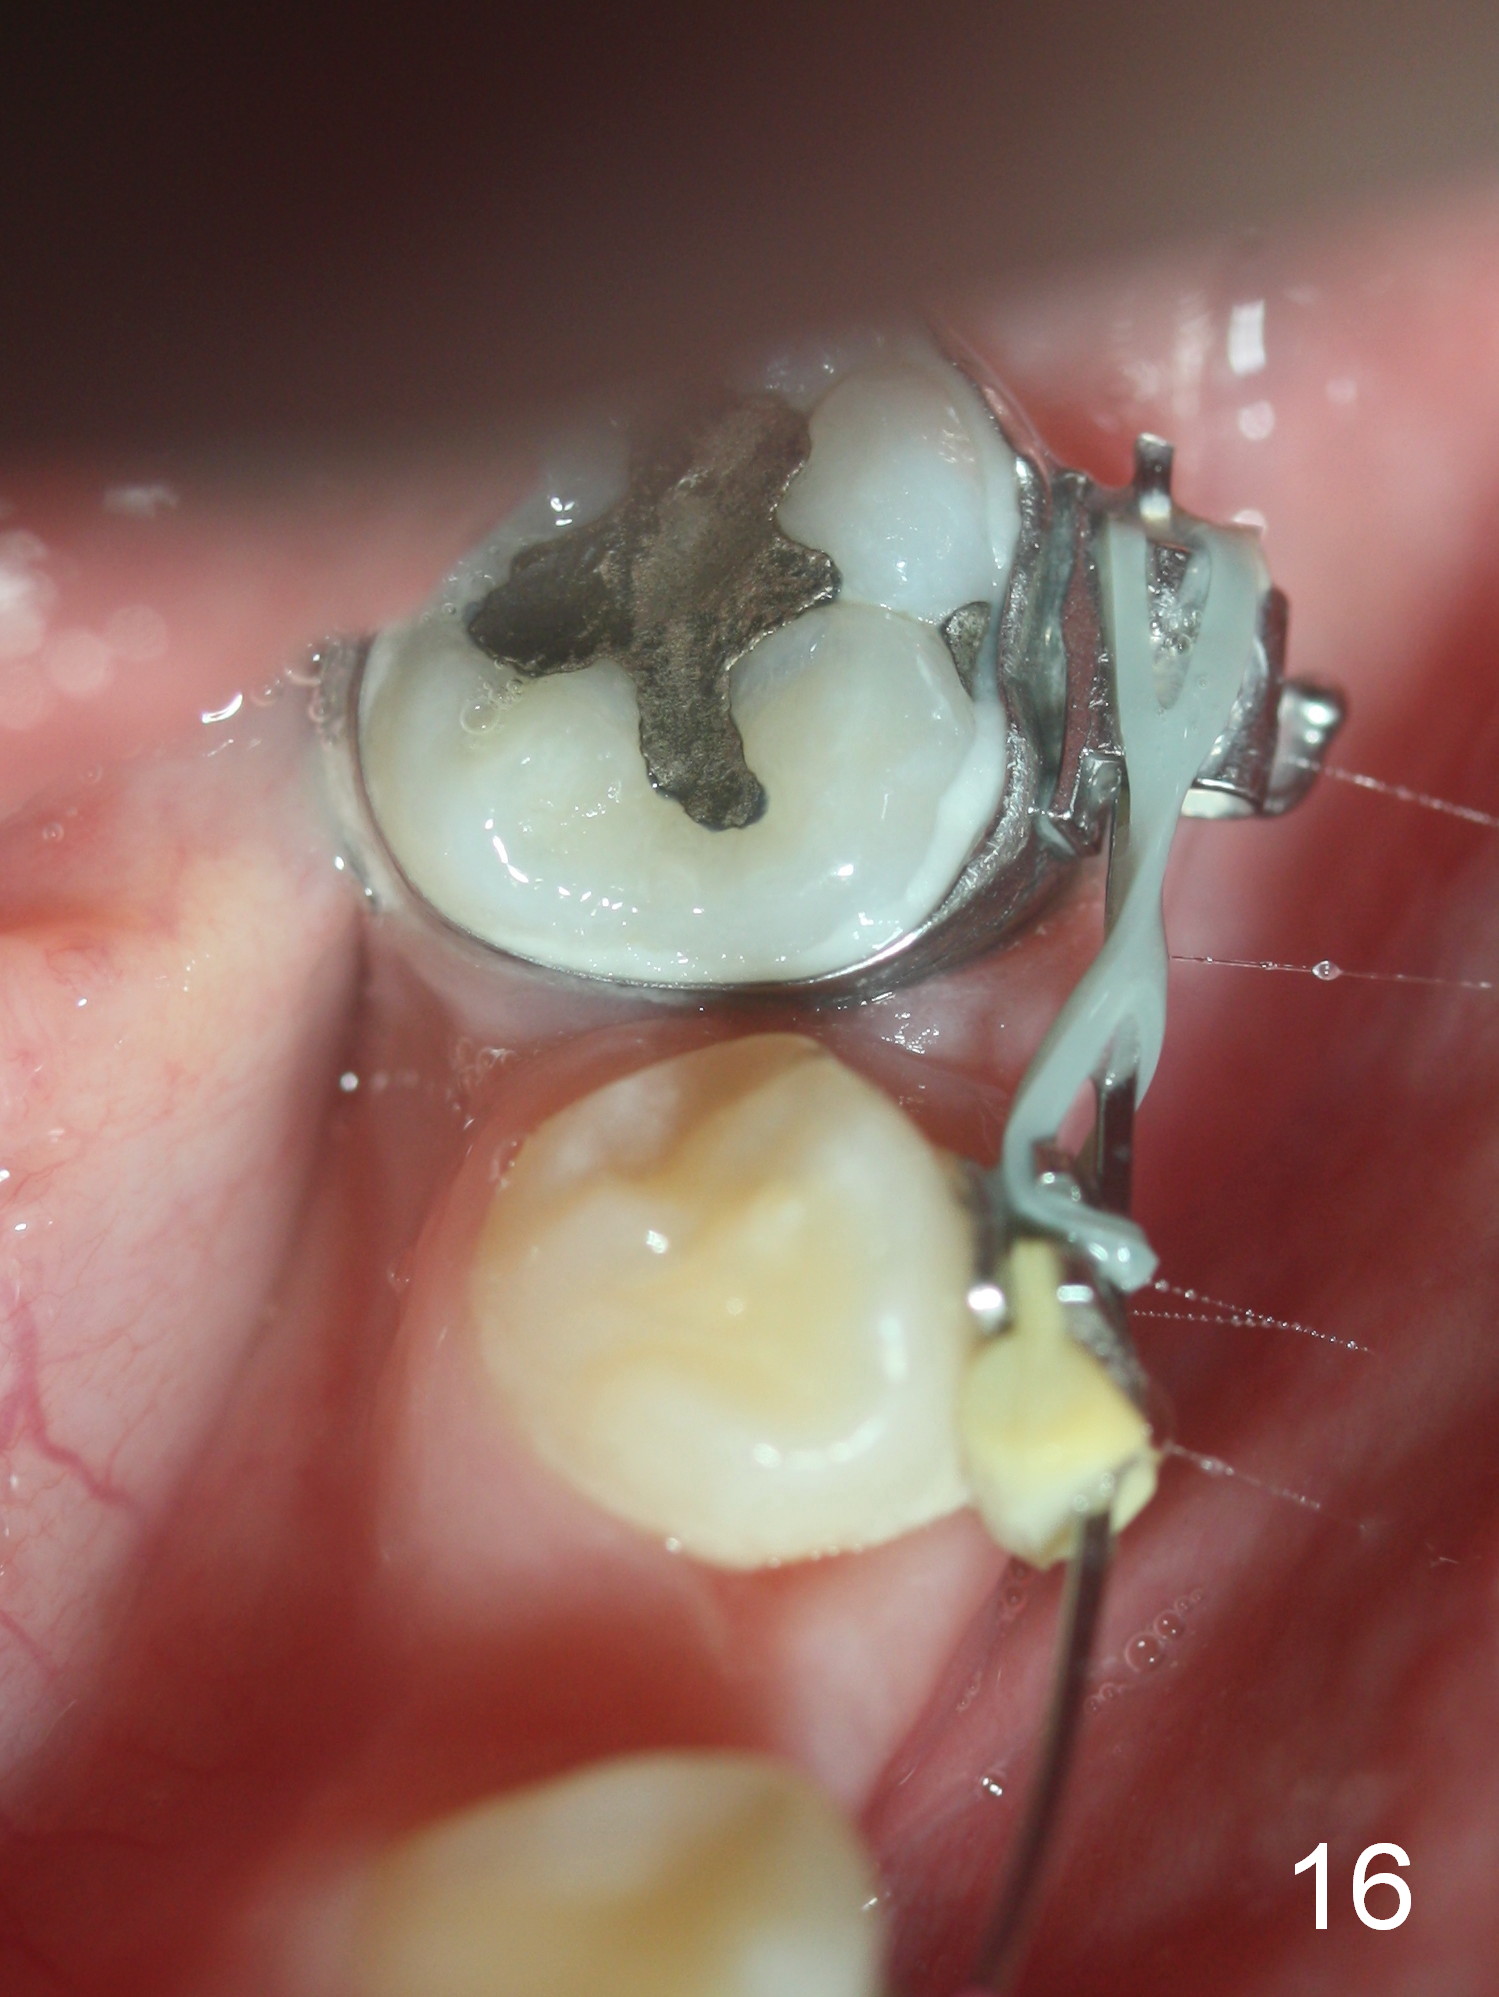

Approximately 4.5 months of power chains between 4s and 6s buccally, U4s contact U6s with rotation (Fig.13,14), while L4s have 1-2 mm to be distalized (Fig.15,16). With placement of lingual buttons on U4s and power chains lingually, the rotation should be corrected. The rotation wedges were placed with ligature wire on the left in the last visit. The patient returns 3 weeks later.